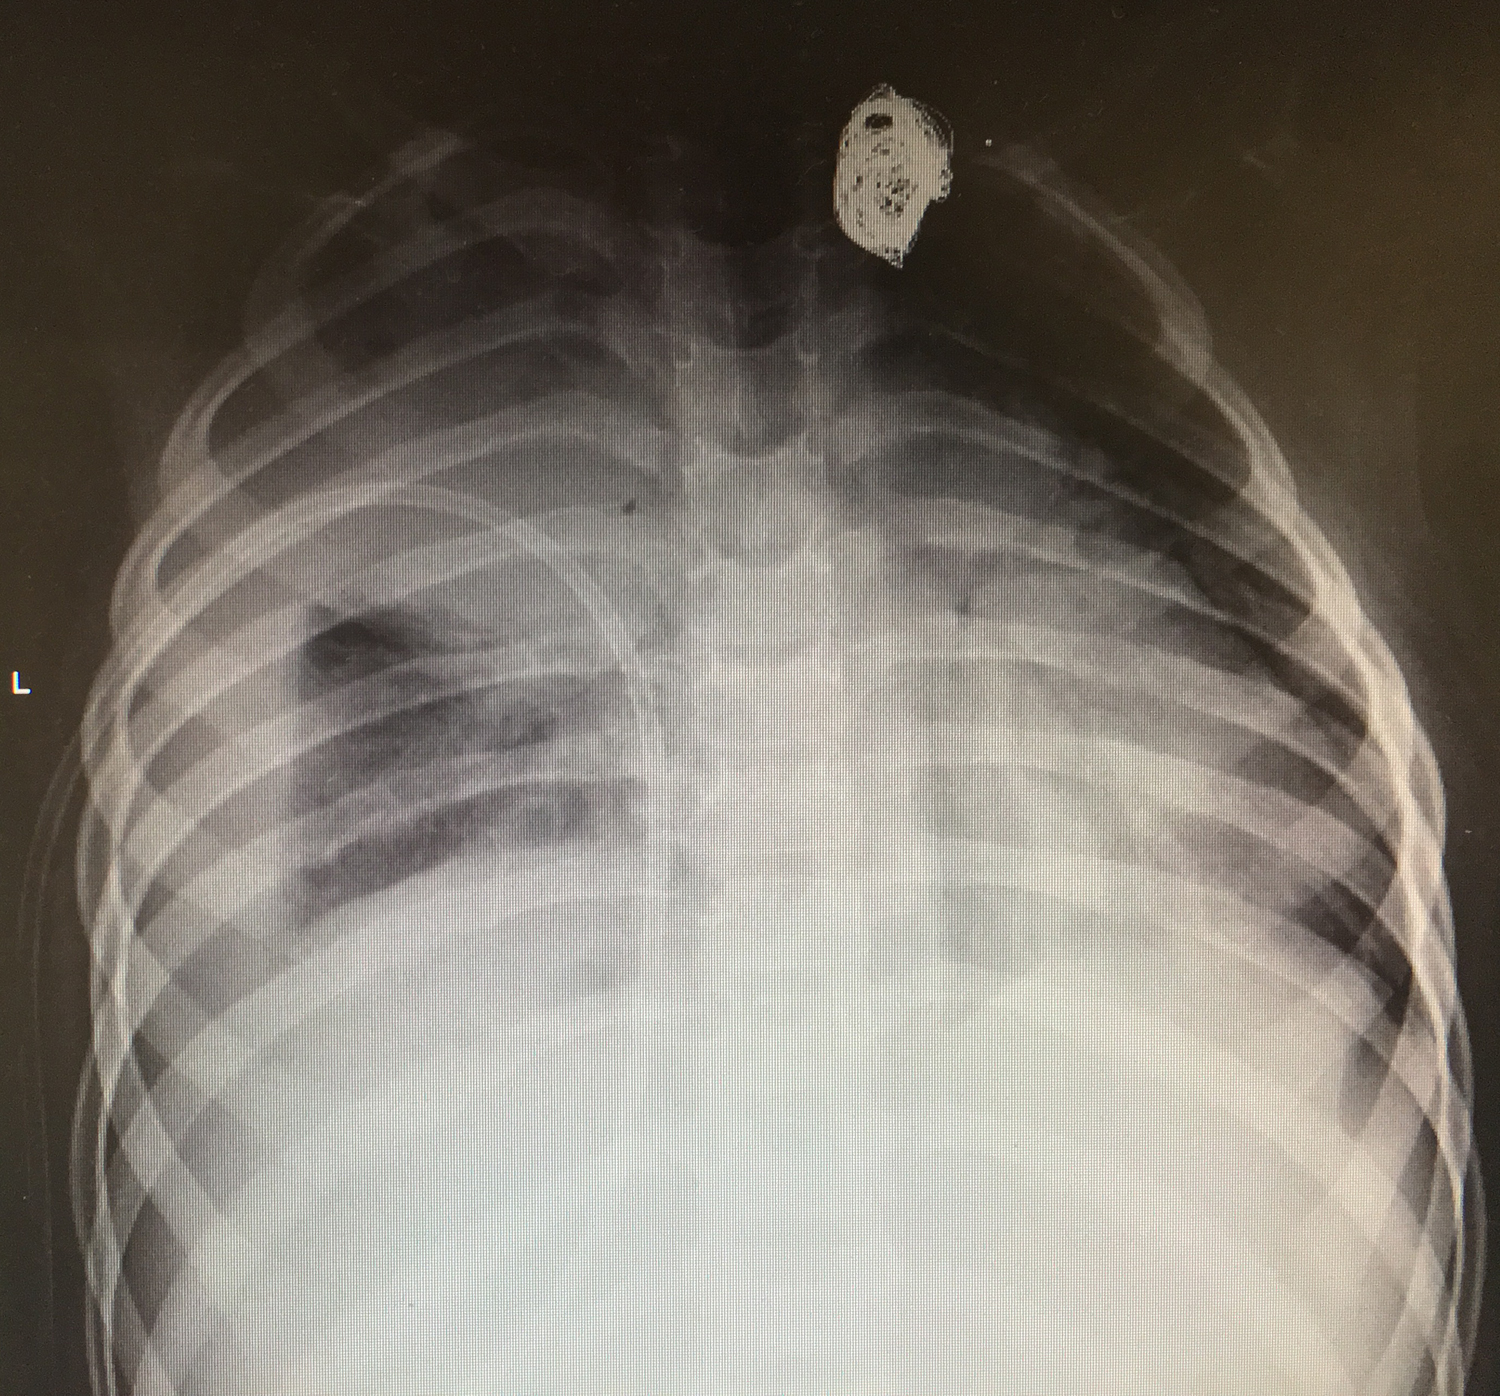

Se traslada a la Unidad de Cuidados Intensivos, se extraen hemocultivos, se inicia tratamiento con cefotaxima y clindamicina. Se coloca un drenaje pleural (pig-tail) conectado a sello de agua con salida de líquido seropurulento abundante de las siguientes características: